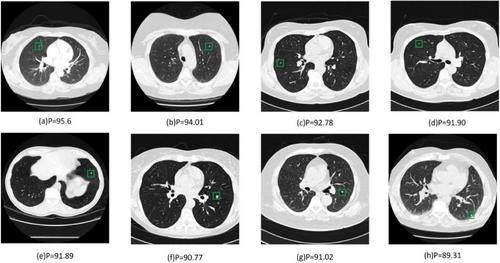

Malignant lung nodules can significantly affect patients' normal lives and, in severe cases, threaten their survival. Owing to the heterogeneity of computed tomography scans and the varying sizes of nodules, physicians often face challenges in diagnosing this condition. Therefore, a novel adaptive multi-channel fusion network (AMCF-Net) is proposed for computer-aided diagnosis of lung nodules. First, a Multi-Channel Fusion Model module is designed, which divides the channels into two parts in specific proportions, effectively extracting multi-scale channel information while reducing network parameters. After the feature maps output at each layer of the AMCF-Net, a novel adaptive depth-wise separable convolution with a squeeze-and-excitation module is designed to adaptively integrate the feature maps of various stages of the AMCF-Net, ensuring that the key lesions of lung nodules are not lost during classification. Finally, a hybrid loss scheme based on an adaptive mixing ratio is proposed to solve the problem of an imbalanced number of positive and negative nodule samples in the dataset. The model achieved the following test results: an accuracy of 90.22%, a specificity of 98.19%, an F1-score of 86.57%, a sensitivity of 86.49%, and a G-mean of 87.72%. Compared with other advanced networks, AMCF-net delivers high-precision lung nodule classification with minimal inference cost. Related codes have been released at: https://github.com/GuYuIMUST/AMCF-net.